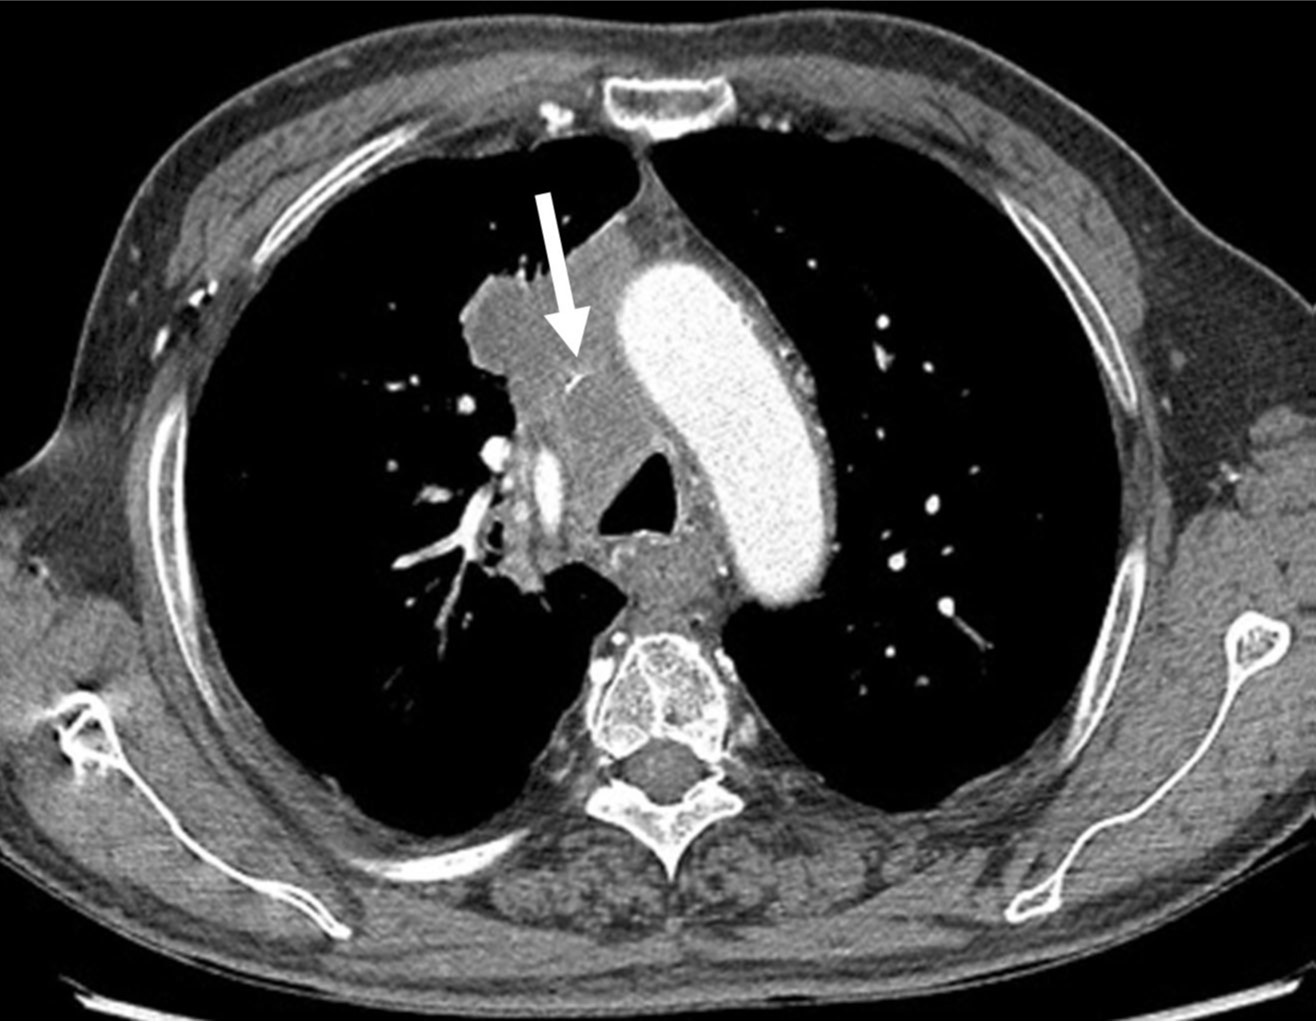

흉부 CT영상에서 폐암의 종격동 침범과 임파절 전이로 인해 상대정맥이 눌려 심하게 좁아져 있다(Fig. 1).

Fig. 1. A

Fig. 1A, 1B. The axial (A) and coronal (B) images of chest CT scans show segmental severe narrowing(arrows) of the superior vena cava resulting from compression by the surrounding malignant tumor with mediastinal lymph node metastasis.